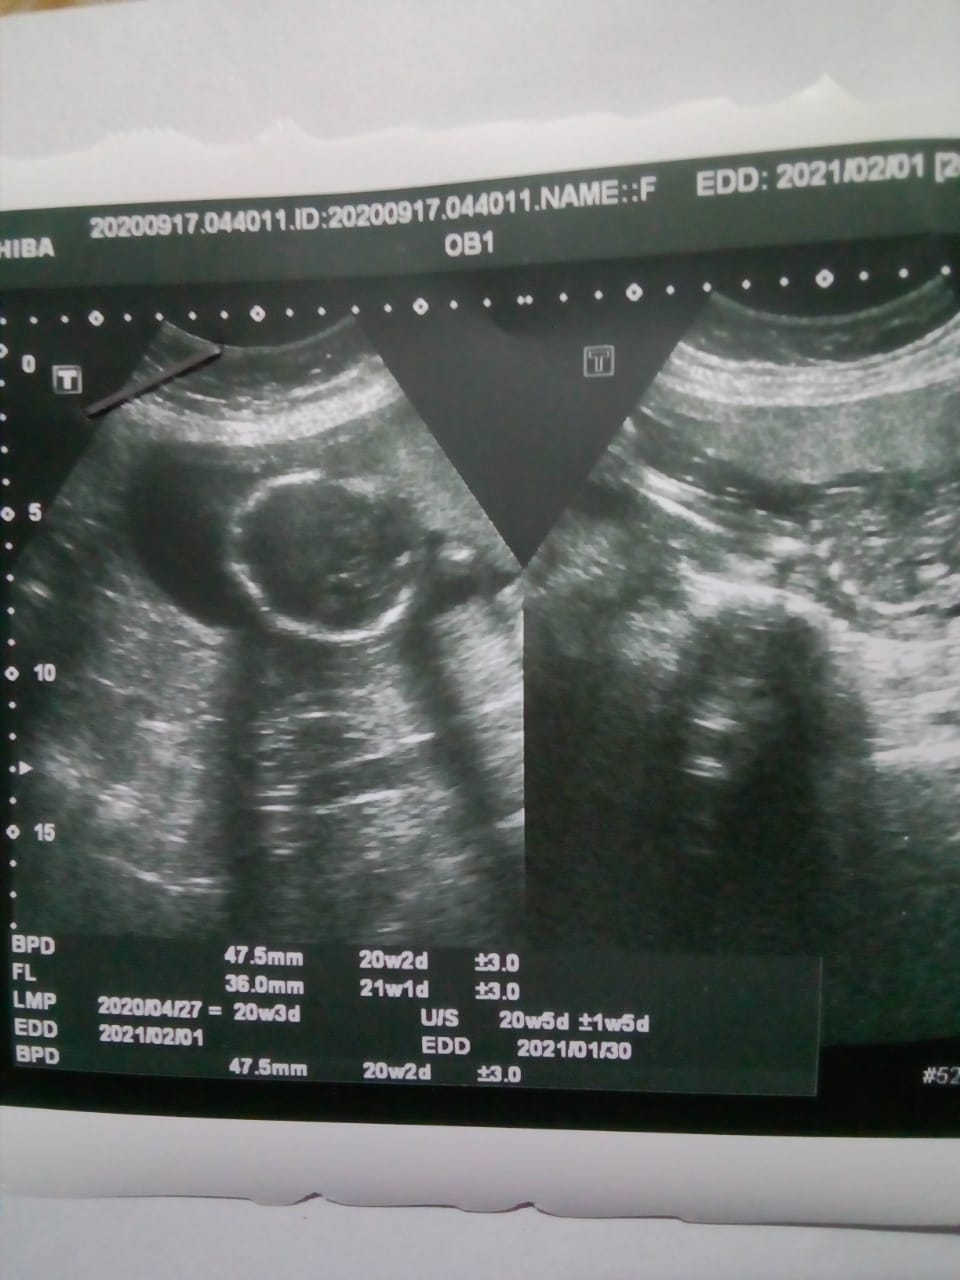

Please guess the gender of my baby 20w 3 days old. I already have three girls.

Do you have other pictures? In these pics, it's just of baby's head.

In the right picture it's hard to tell but it looks like just part of baby's spine. There's no genitalia in any of these pictures.